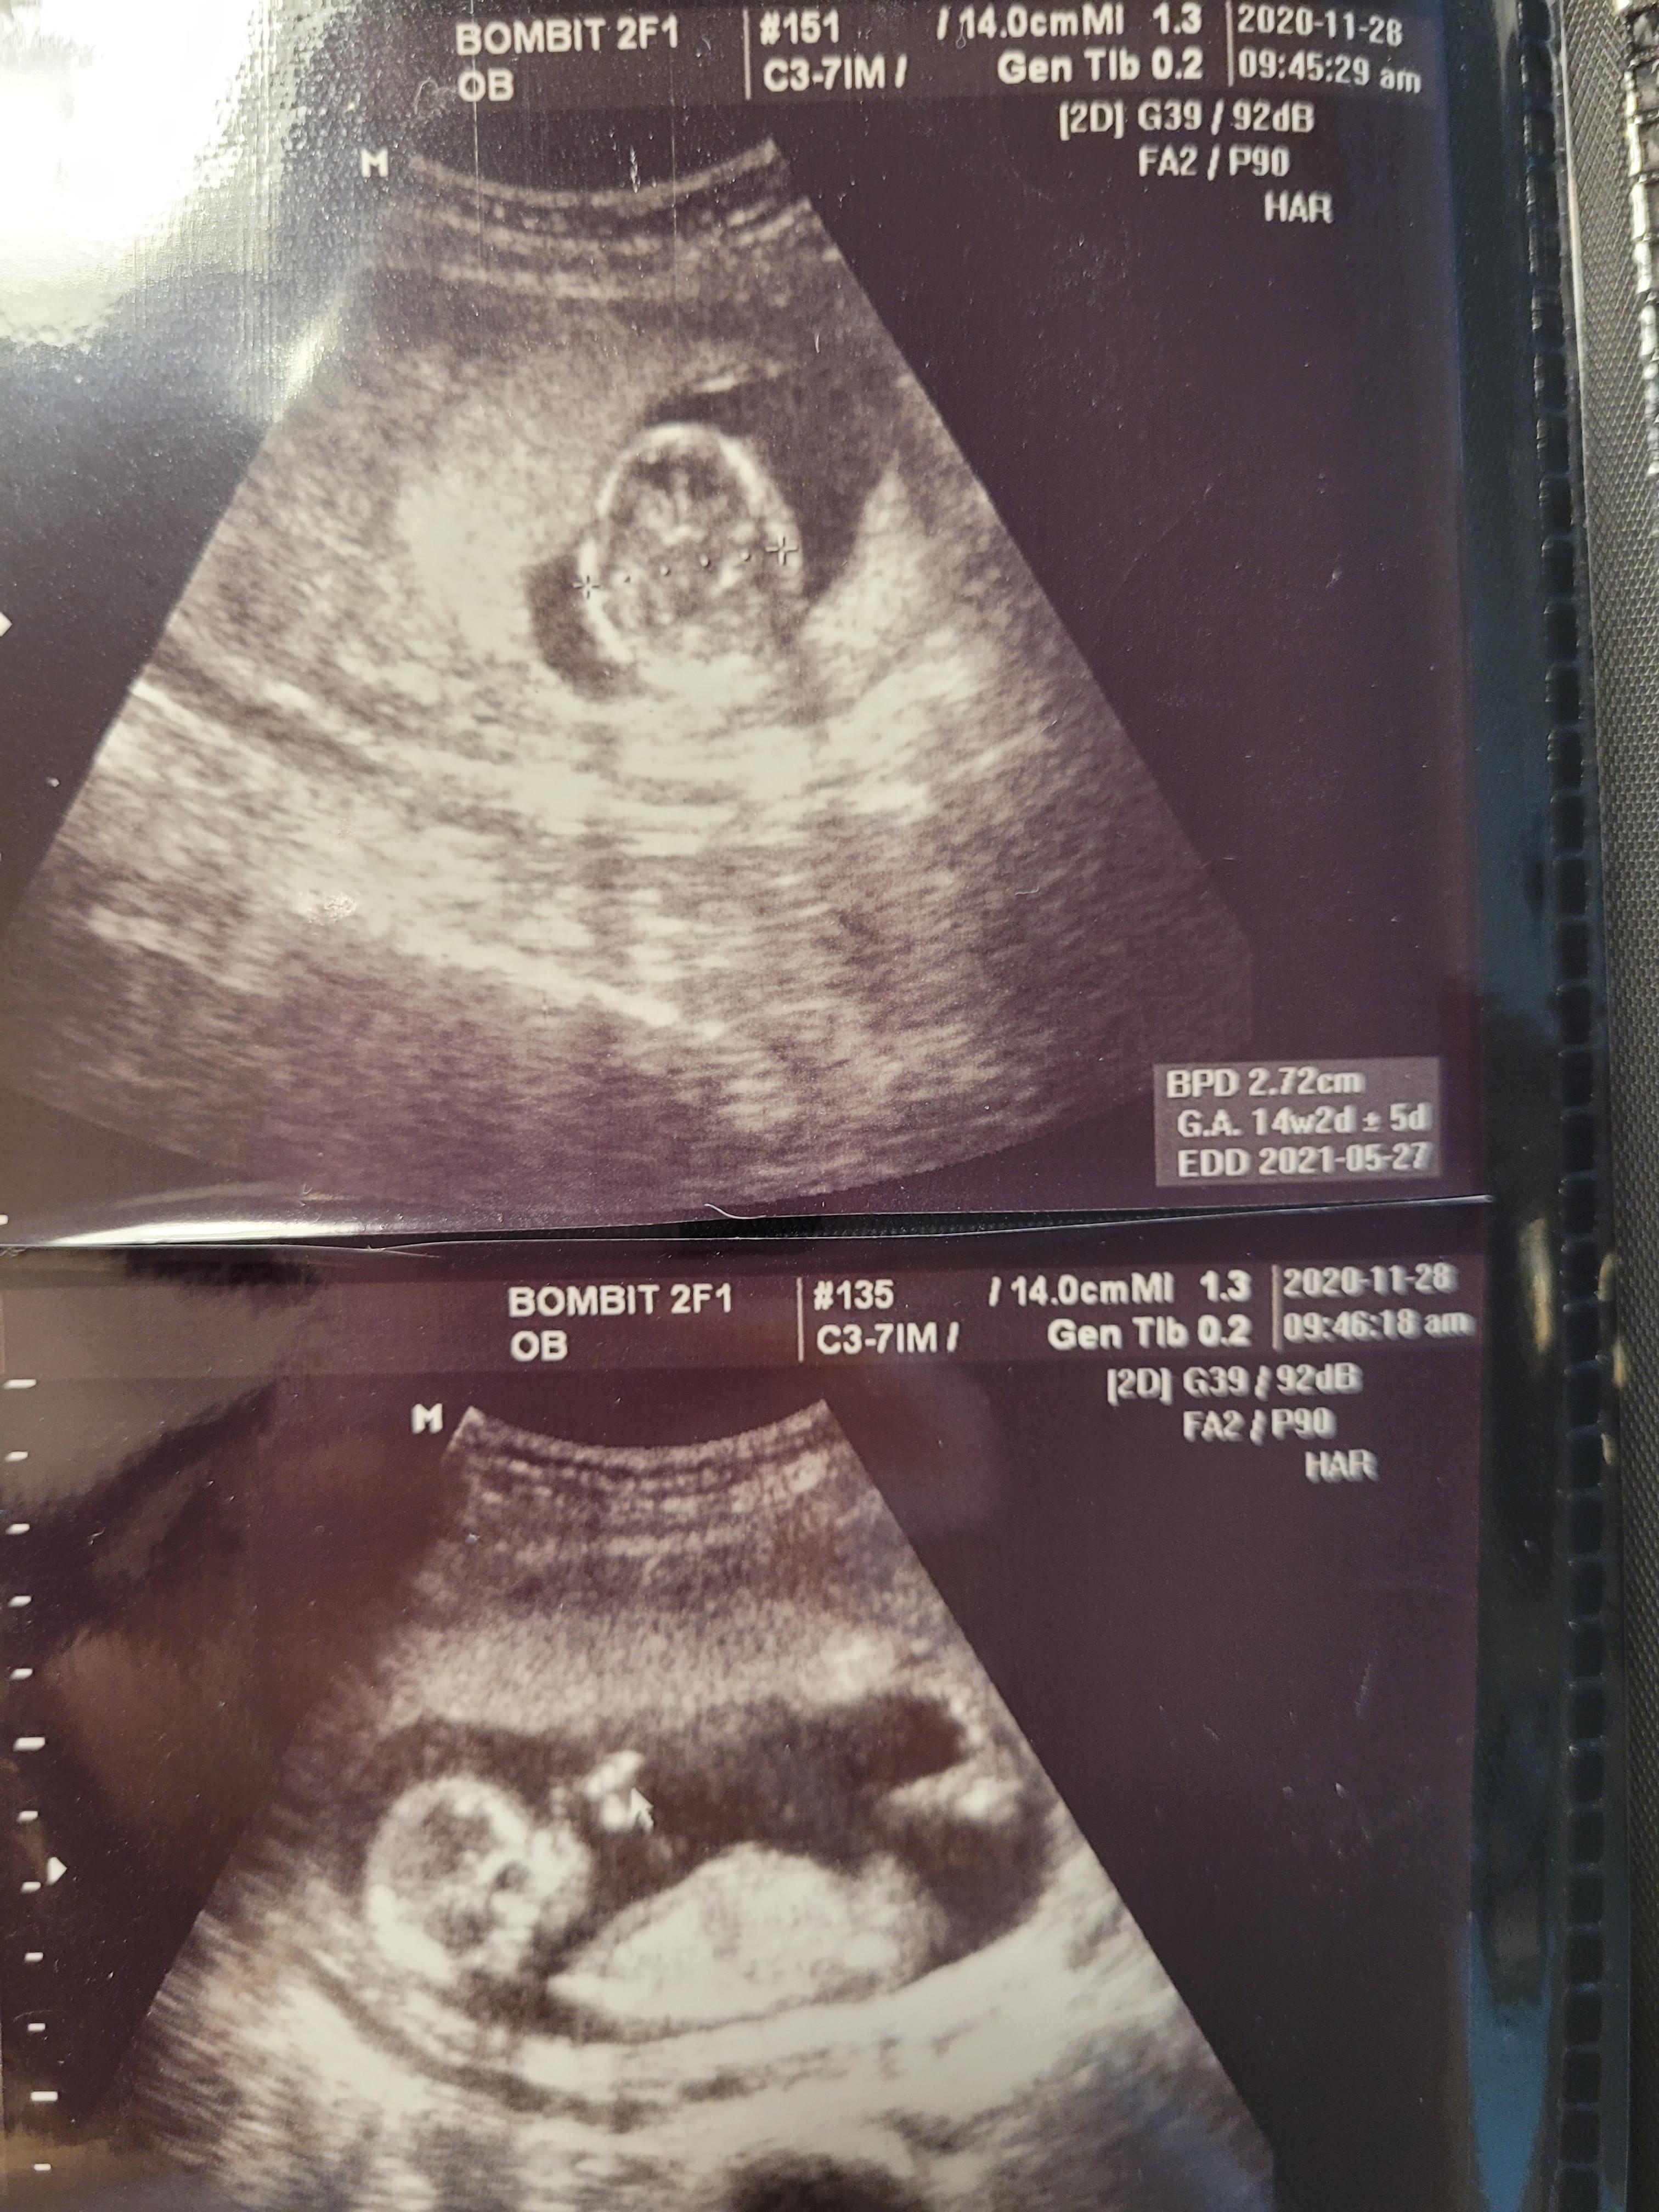

먼저 초음파를 보기로했고요.

걱정과 달리, 행복이는 아주 잘 자라고 있었어요.

아무 문제도 없었고요.

입덧이 끝나서인지 원래 주수에 맞게 잘 자라고있었는데 이제 더더더 잘 크고있네요.

주수보다 1주일이상 큰 상태였고, 이때부터 쭉 원장님도 아가가 발육이 좋다고 늘 칭찬해주셨어요.